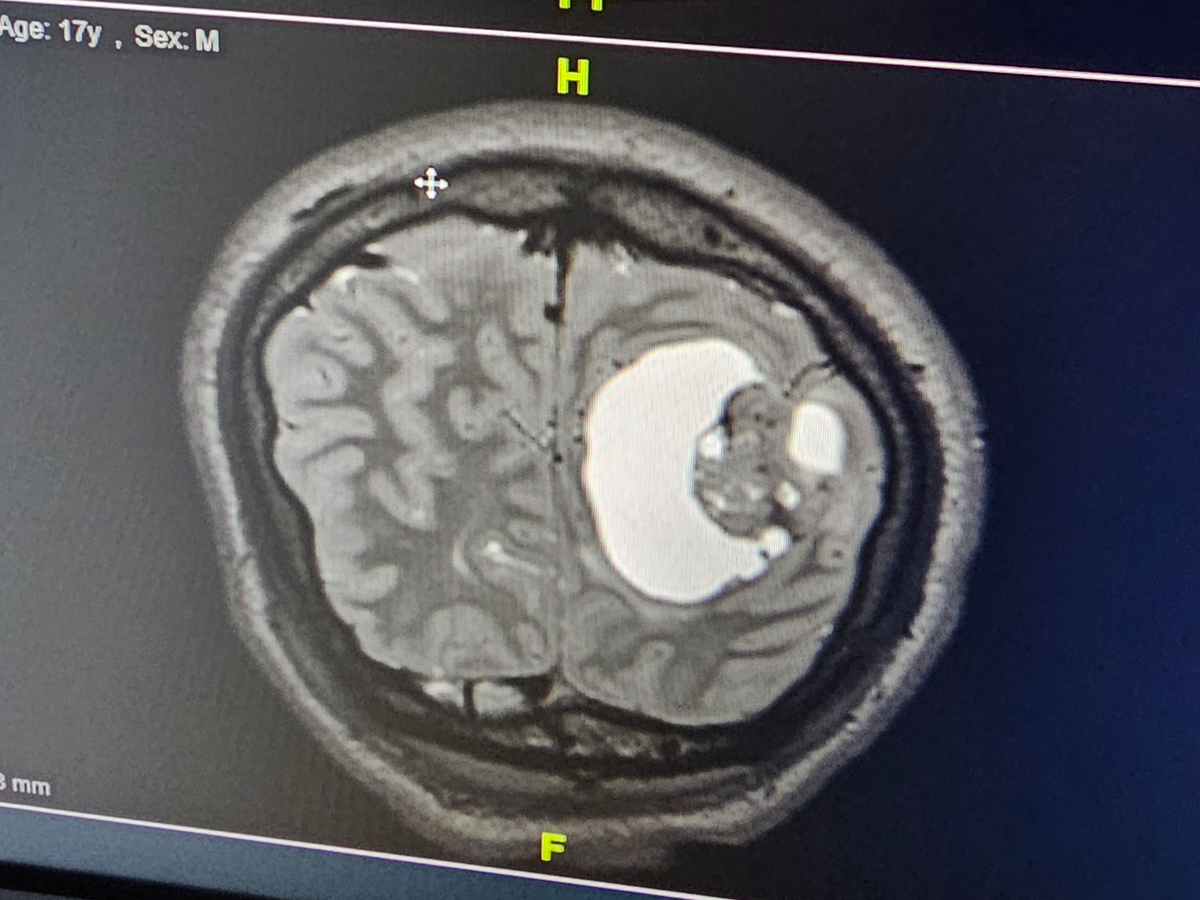

It started when Mason was complaining of having headaches...that would not completely go away. It got better at times, but it came to the point where I had to take him to the hospital because he was telling me something was wrong. The hospital gave him the classic migraine cocktail and sent us home. A couple more days go by and Mason wants to go to the hospital again- insisting, saying that something is not right. So i demanded the hospital did something- not medicine- but look at his head, to see if something was wrong. They did a CT-scan, and the unimaginable results came back- he had a tumor in his brain. We were surprised because you never expect that in a healthy 17 year old. At that point they gave us an envelope with specific instructions to go straight to Akron Childrens Hospital. We spent the night and first thing the next morning they did a very detailed MRI- full scan with function so they could better understand exactly what was there in his brain. Within 24hrs we were in brain surgery, having this large tumor removed. 20 staples and 5 sleepless nights in the hospital, only to be told to wait for the biopsy results even longer. Our experience at Akron Childrens Hospital was best case scenario for the situation tho- having a great Neurologist and amazing team of specialists. So we waited- an entire month before we got the call. They explained that we needed to come to the hospital, Mason included to go over what they found. I was not prepared for what they would tell us....

PLEOMORPHIC XANTHOASTROCYTOMA! A very rare type of brain cancer with less than 100 cases a year! I held it all together up until that day. We came home, I waited until I could be alone and away from anyone, and I fell apart. As a mother- u never want your children to suffer, to be in pain, to go through anything remotely close to something like brain cancer.